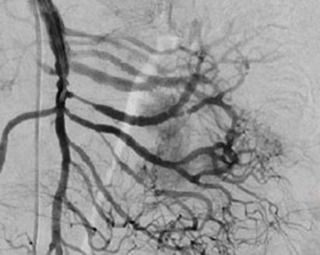

La decisión de realizar una angiografía de urgencia en individuos con una hemorragia profusa de tubo digestivo bajo que se manifiesta por inestabilidad hemodinámica continua y hematoquezia se basa en varios factores clave que hacen que esta sea una estrategia médica apropiada y, en muchos casos, crítica.

La angiografía es una técnica de diagnóstico en tiempo real que permite a los médicos localizar y tratar la fuente de la hemorragia de manera inmediata. Esto es especialmente importante cuando la hemorragia es severa y el paciente está en peligro de shock hemorrágico.

La angiografía puede ayudar a identificar la fuente exacta de la hemorragia en el tubo digestivo bajo, como un vaso sanguíneo dañado o una malformación vascular. Esta información es crucial para determinar el mejor enfoque terapéutico.

La angiografía terapéutica permite a los radiólogos intervencionistas llevar a cabo procedimientos para detener la hemorragia en el momento en que se identifica la fuente. Esto puede incluir la embolización de arterias sangrantes o la colocación de stents para restaurar el flujo sanguíneo adecuado.

La angiografía es especialmente efectiva para detectar y tratar hemorragias arteriales agudas, que son una causa común de hemorragia profusa en el tubo digestivo bajo. La colonoscopia y la gammagrafía son menos eficaces en la detección de hemorragias arteriales.